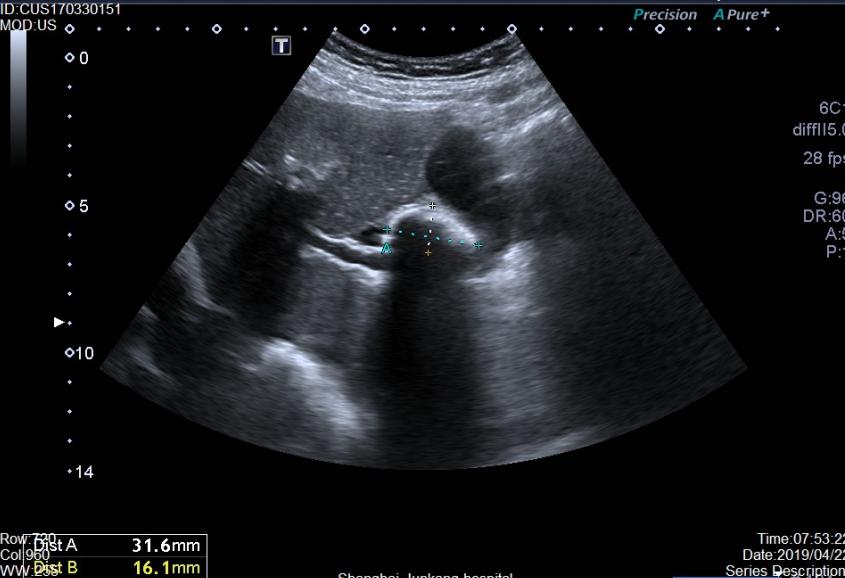

胆结石